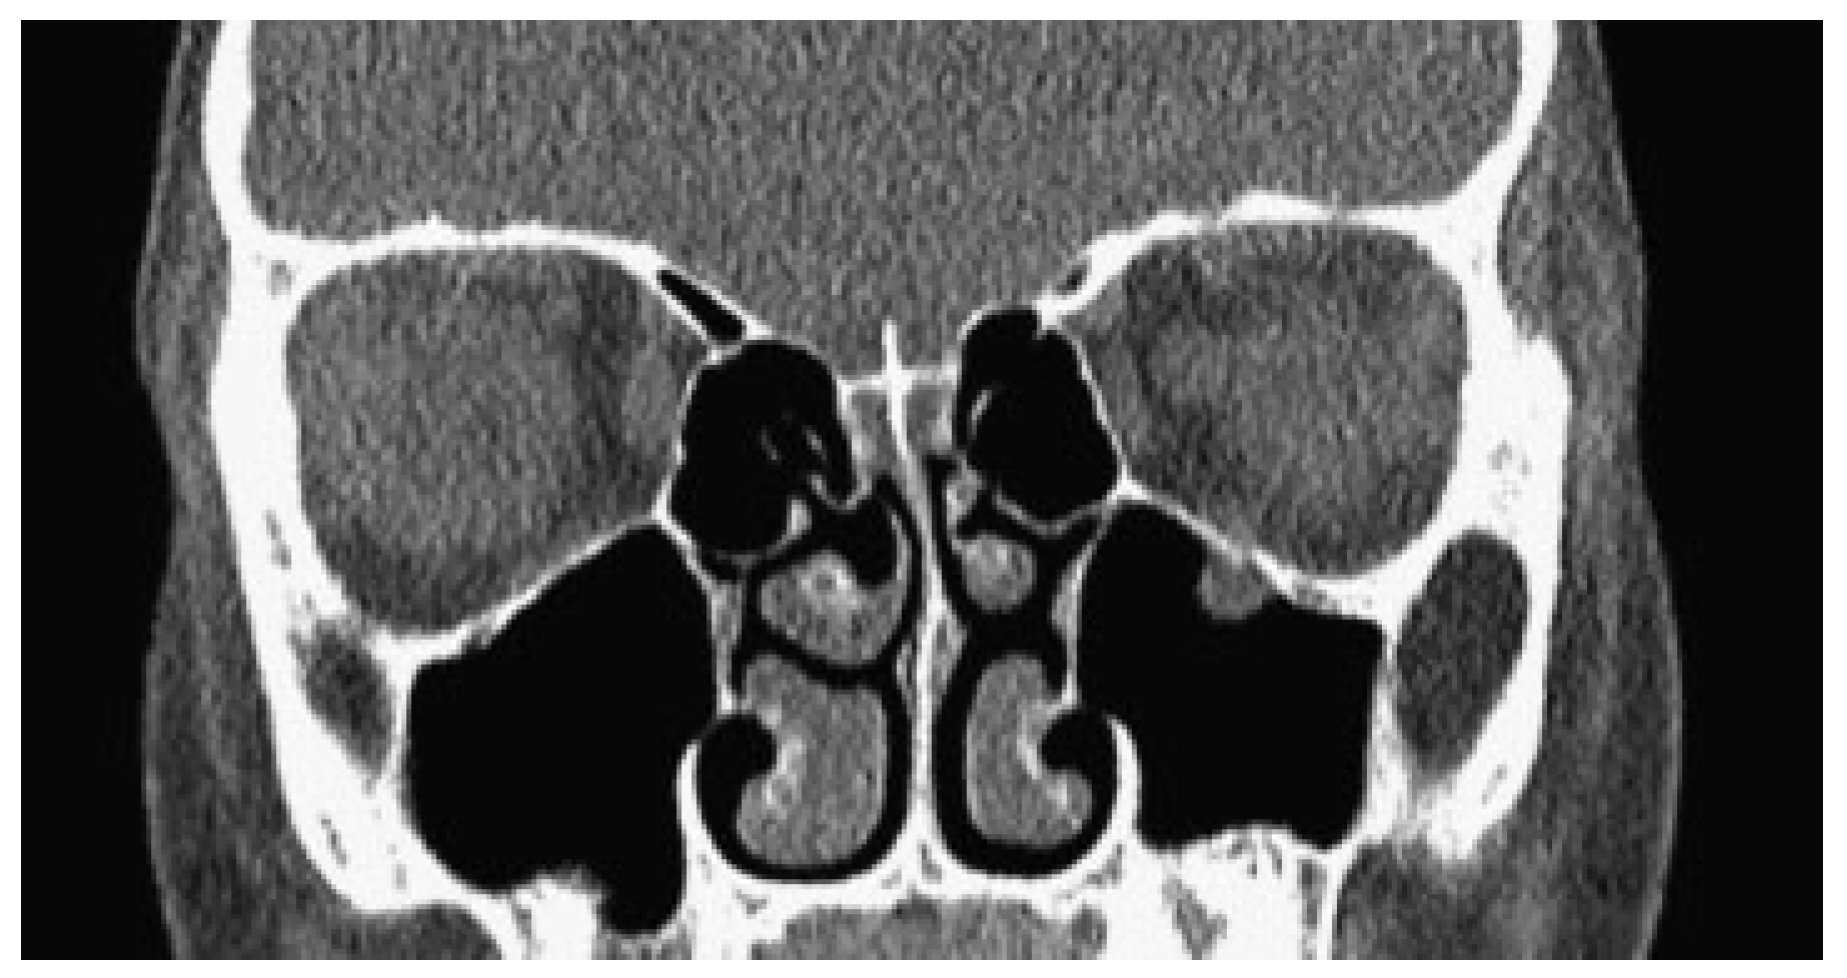

Figure 6. CT scan of a 9-year-old girl with a severe up-gaze deficit from a left-sided nondisplaced orbital floor fracture with entrapment of the inferior rectus muscle.

Extraocular muscle entrapment in a nondisplaced orbital fracture is seen near exclusively in the pediatric population [1,2]. Compared with adults, the bones of children contain a higher proportion of osteocytes relative to osteoblasts, and decreased mineralization, leading to increased compliance [3]. Consequently, pediatric orbital fractures may not have the characteristic orbital fracture bone fragmentation pattern seen in adults with displacement of orbital bones and orbital contents often into adjacent sinuses. Instead, after blunt periorbital trauma in a child, the orbital floor bones may become temporarily displaced in a hinge-like fashion before snapping back into anatomic, nondisplaced position. In adult and pediatric cases of orbital trauma, simultaneous pressure on the globe at the time of facial impact pressurizes and displaces the orbital contents through the fracture. In children, muscle entrapment can occur if the contents do not escape before the compliant bone fragment snaps back into place (as seen in Figure 6). This fracture pattern was first described in 1965 by Soll and Poley, who coined the term “trapdoor fracture”[4]. Although a case of inferior rectus muscle sheath entrapment in an adult patient occurring in a non-displaced fracture has been reported [5], review of the literature suggests that extraocular muscle entrapment is extremely rare in the adult subgroups [2,6]. Similarly, a case of medial rectus entrapment in a nondisplaced medial wall fracture has been reported [7], but review of all reported cases of medial rectus entrapment appears to be near exclusive to children [8].